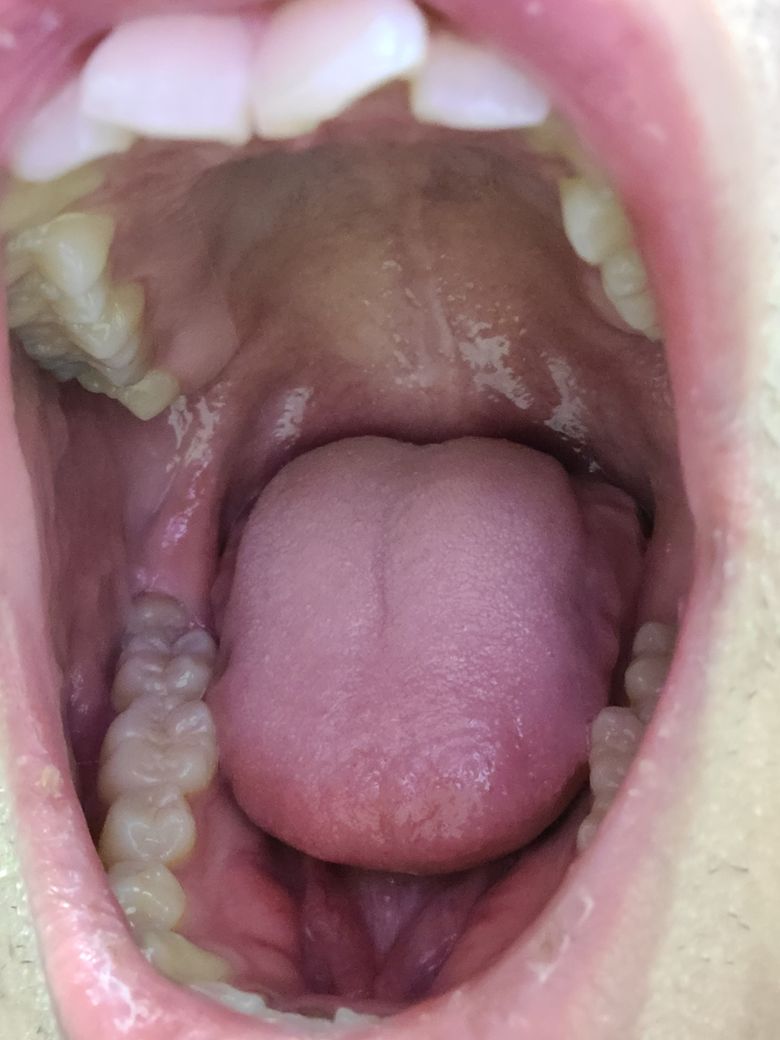

사랑니 충치인지 어금니 충치인지 질문입니다

몇일전에 밥먹다가 우득소리가 나고 약 3~4일 욱씬거리고 물마시면 매우 시린 증상 있었습니다. 카메라로 보니까 충치가 보이는거 같은데 사랑니쪽 충치인가요 어금니쪽 충치인가요?

그리고 충치는 심한상태일까요?

그리고 사랑니는 가끔씩 아픈적 있긴했지만 우득소리가 나느건 처음이라 혹시 치아가 깨졌을 가능성도 있을까요

• 2번 째 사진

사랑니에도 그리고 앞쪽 어금니에도 충치가 보입니다. 정확한 것은 x-ray 등을 찍어봐야 알 수 있을 것으로 보이며 임상 검사로 인하여 해당 부위도 긁어보아야 합니다. 또한 치아가 파절되었을 수도 있으므로 통증 및 불편감이 크다면 가까운 치과 방문 후 평가를 받아보시길 바랍니다.

지금처럼 나있는 사랑니는 무조건 빼시는 것이 좋습니다. 치과에 내원하여 빼시고 앞의 치아와 사이에 충치가 있을 가능성도 있어보입니다.

사진상으로 보면 아래 쪽에 부분매복 사랑니가 잇으신거 같습니다. 정확한건 치과에 가셔서 직접 검진을 받아보시고 엑스레이 사진을 찍어보시는게 좋을것같습니다.